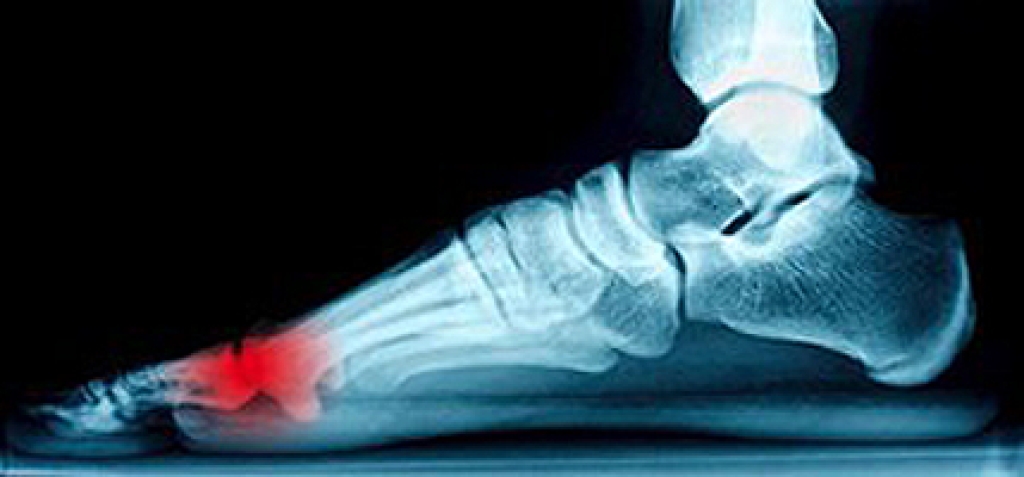

Cracked Heels

Cracked heels appear unappealing and can make it harder for you walk around in sandals. Aside from looking unpleasant, cracked heels can also tear stockings, socks, and wear out your shoes. There are several methods to help restore a cracked heel and prevent further damage.